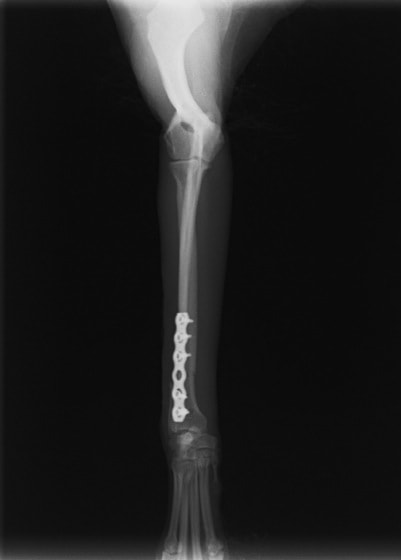

症例3:キルシュナーワイヤーのピンニングによる整復

ペルシャ猫 11ヶ月齢 雄

他院にて左大腿骨遠位の成長板骨折(salter-harrisⅠ型)が認められており、治療相談を目的として来院。当院にて、キルシュナーワイヤーを用いたピンニングにより骨折部位の整復を行いました。術後の経過は良好で、現在も経過観察中です。

術前レントゲン

術後レントゲン